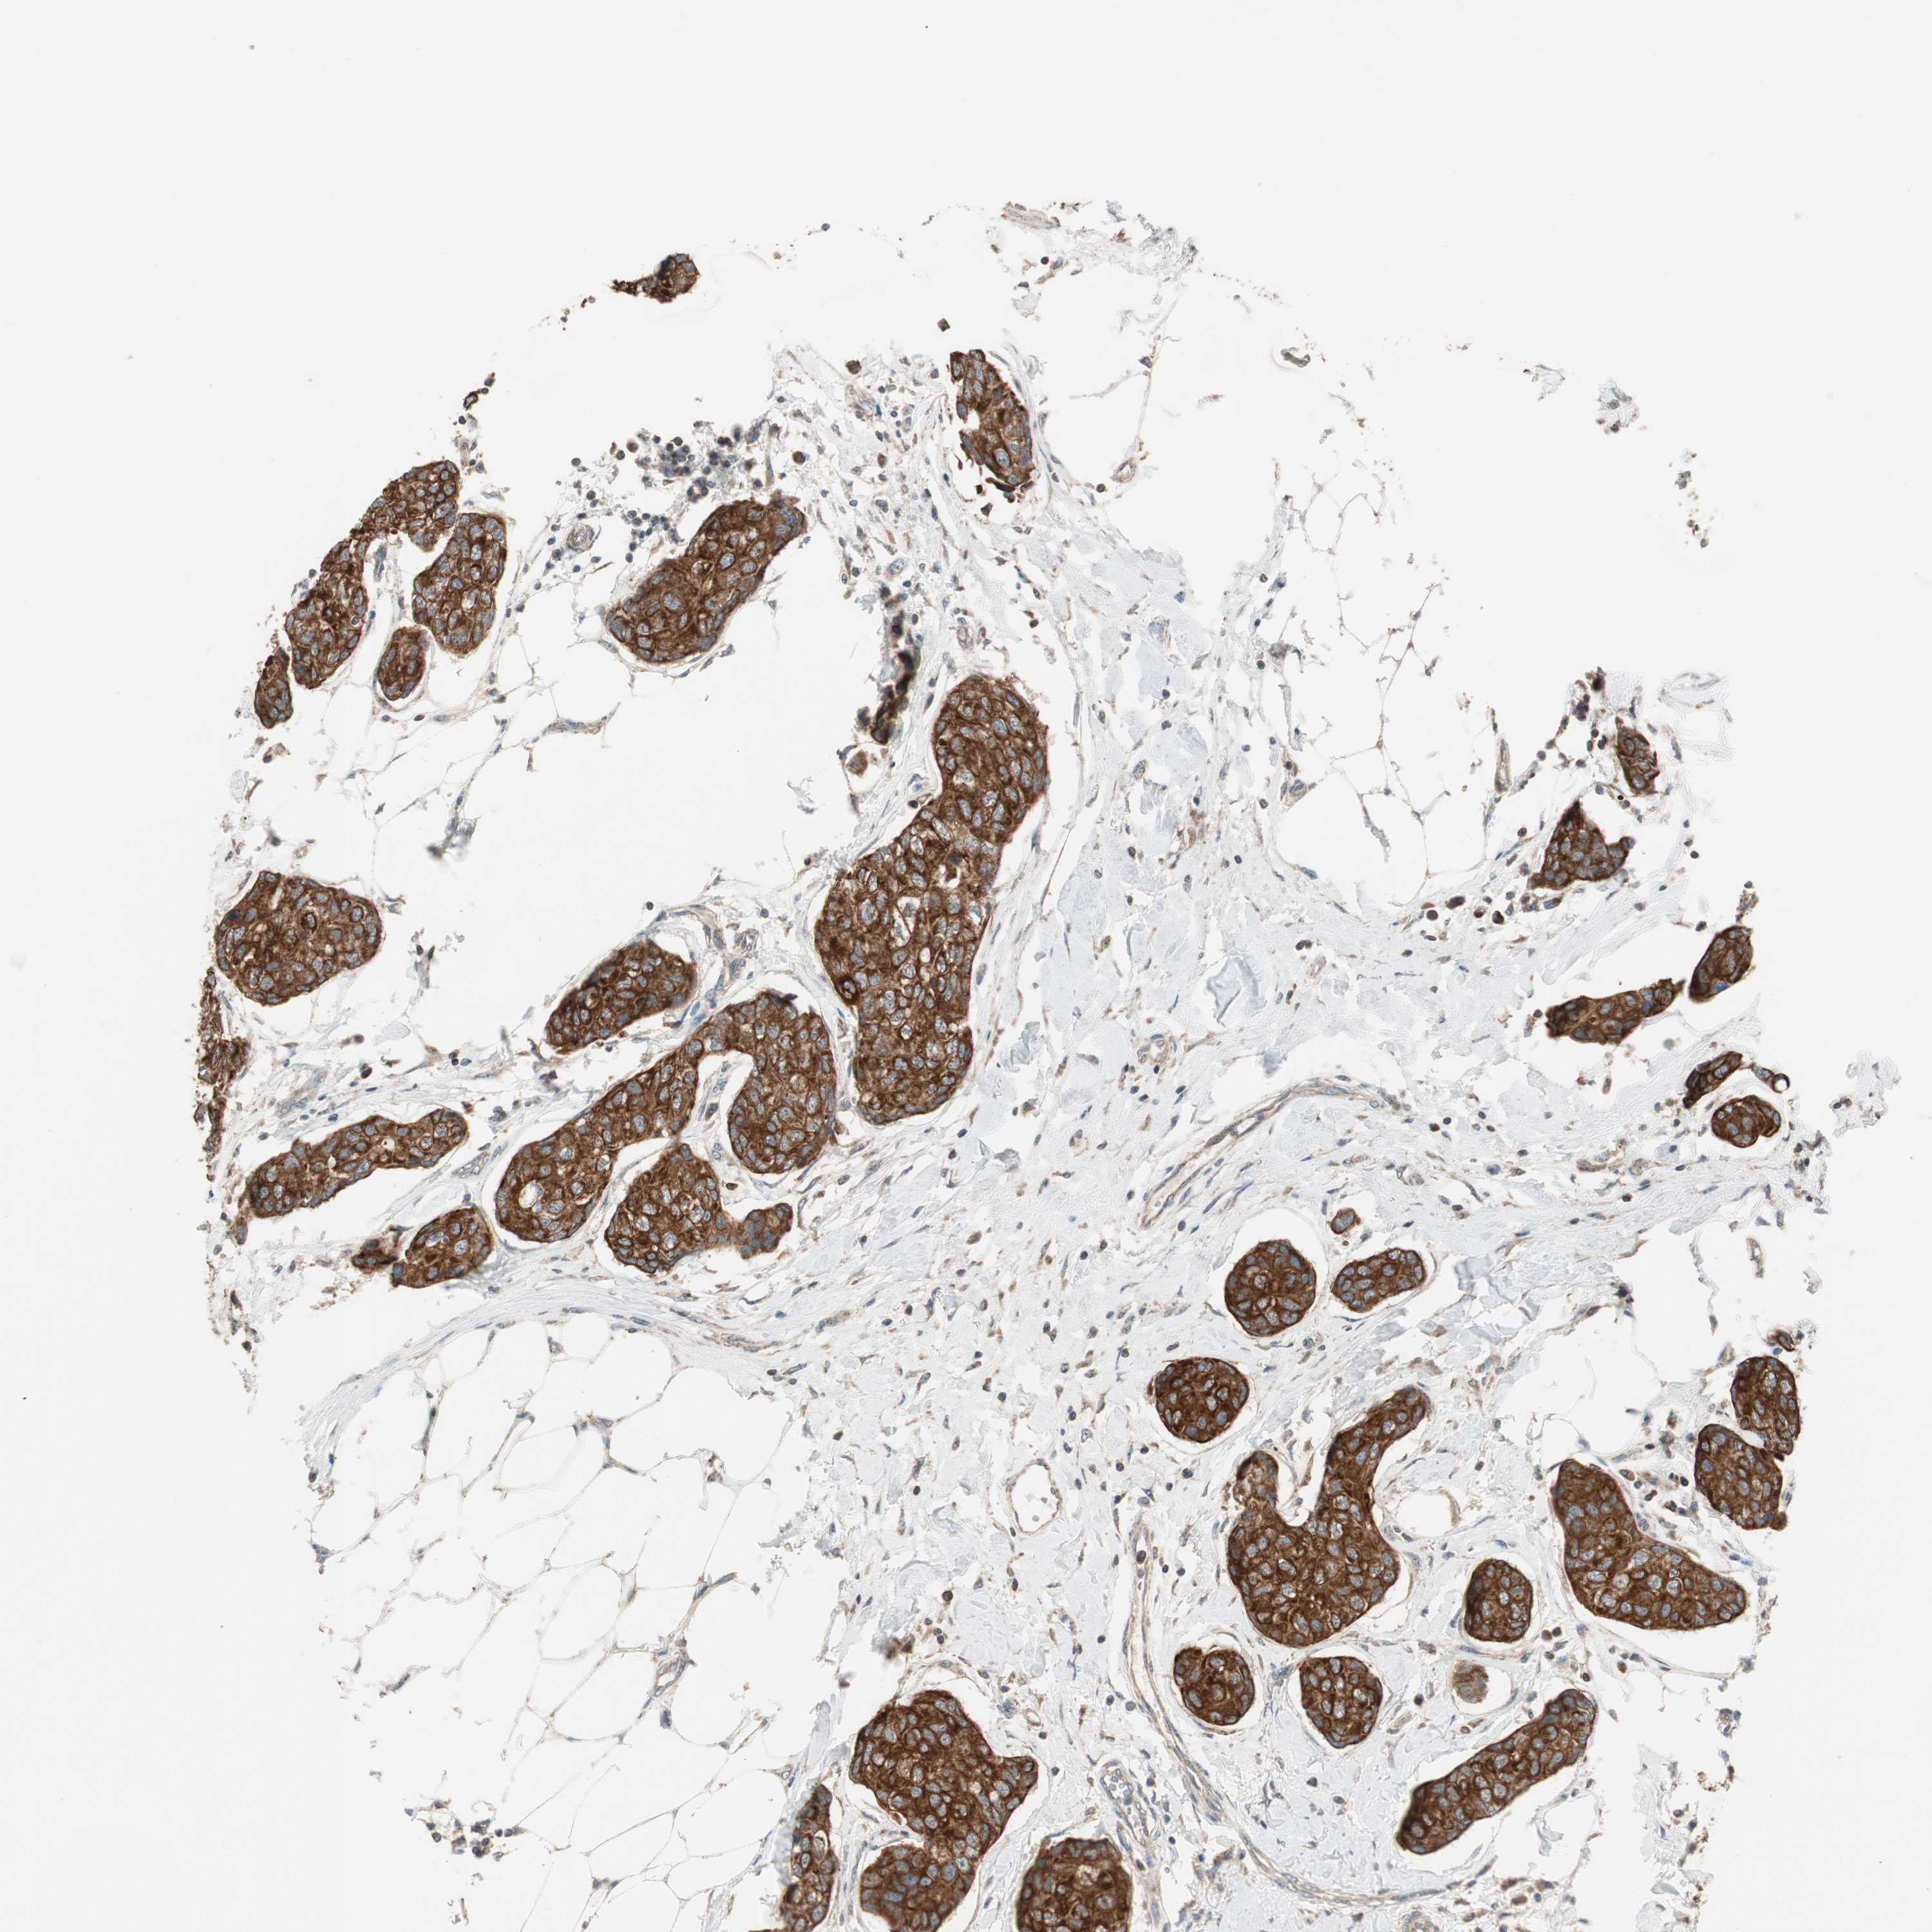

CANCER BREAST CANCER Show tissue menu

BRCA TCGA BRCA VALIDATION PROTEIN EXPRESSION